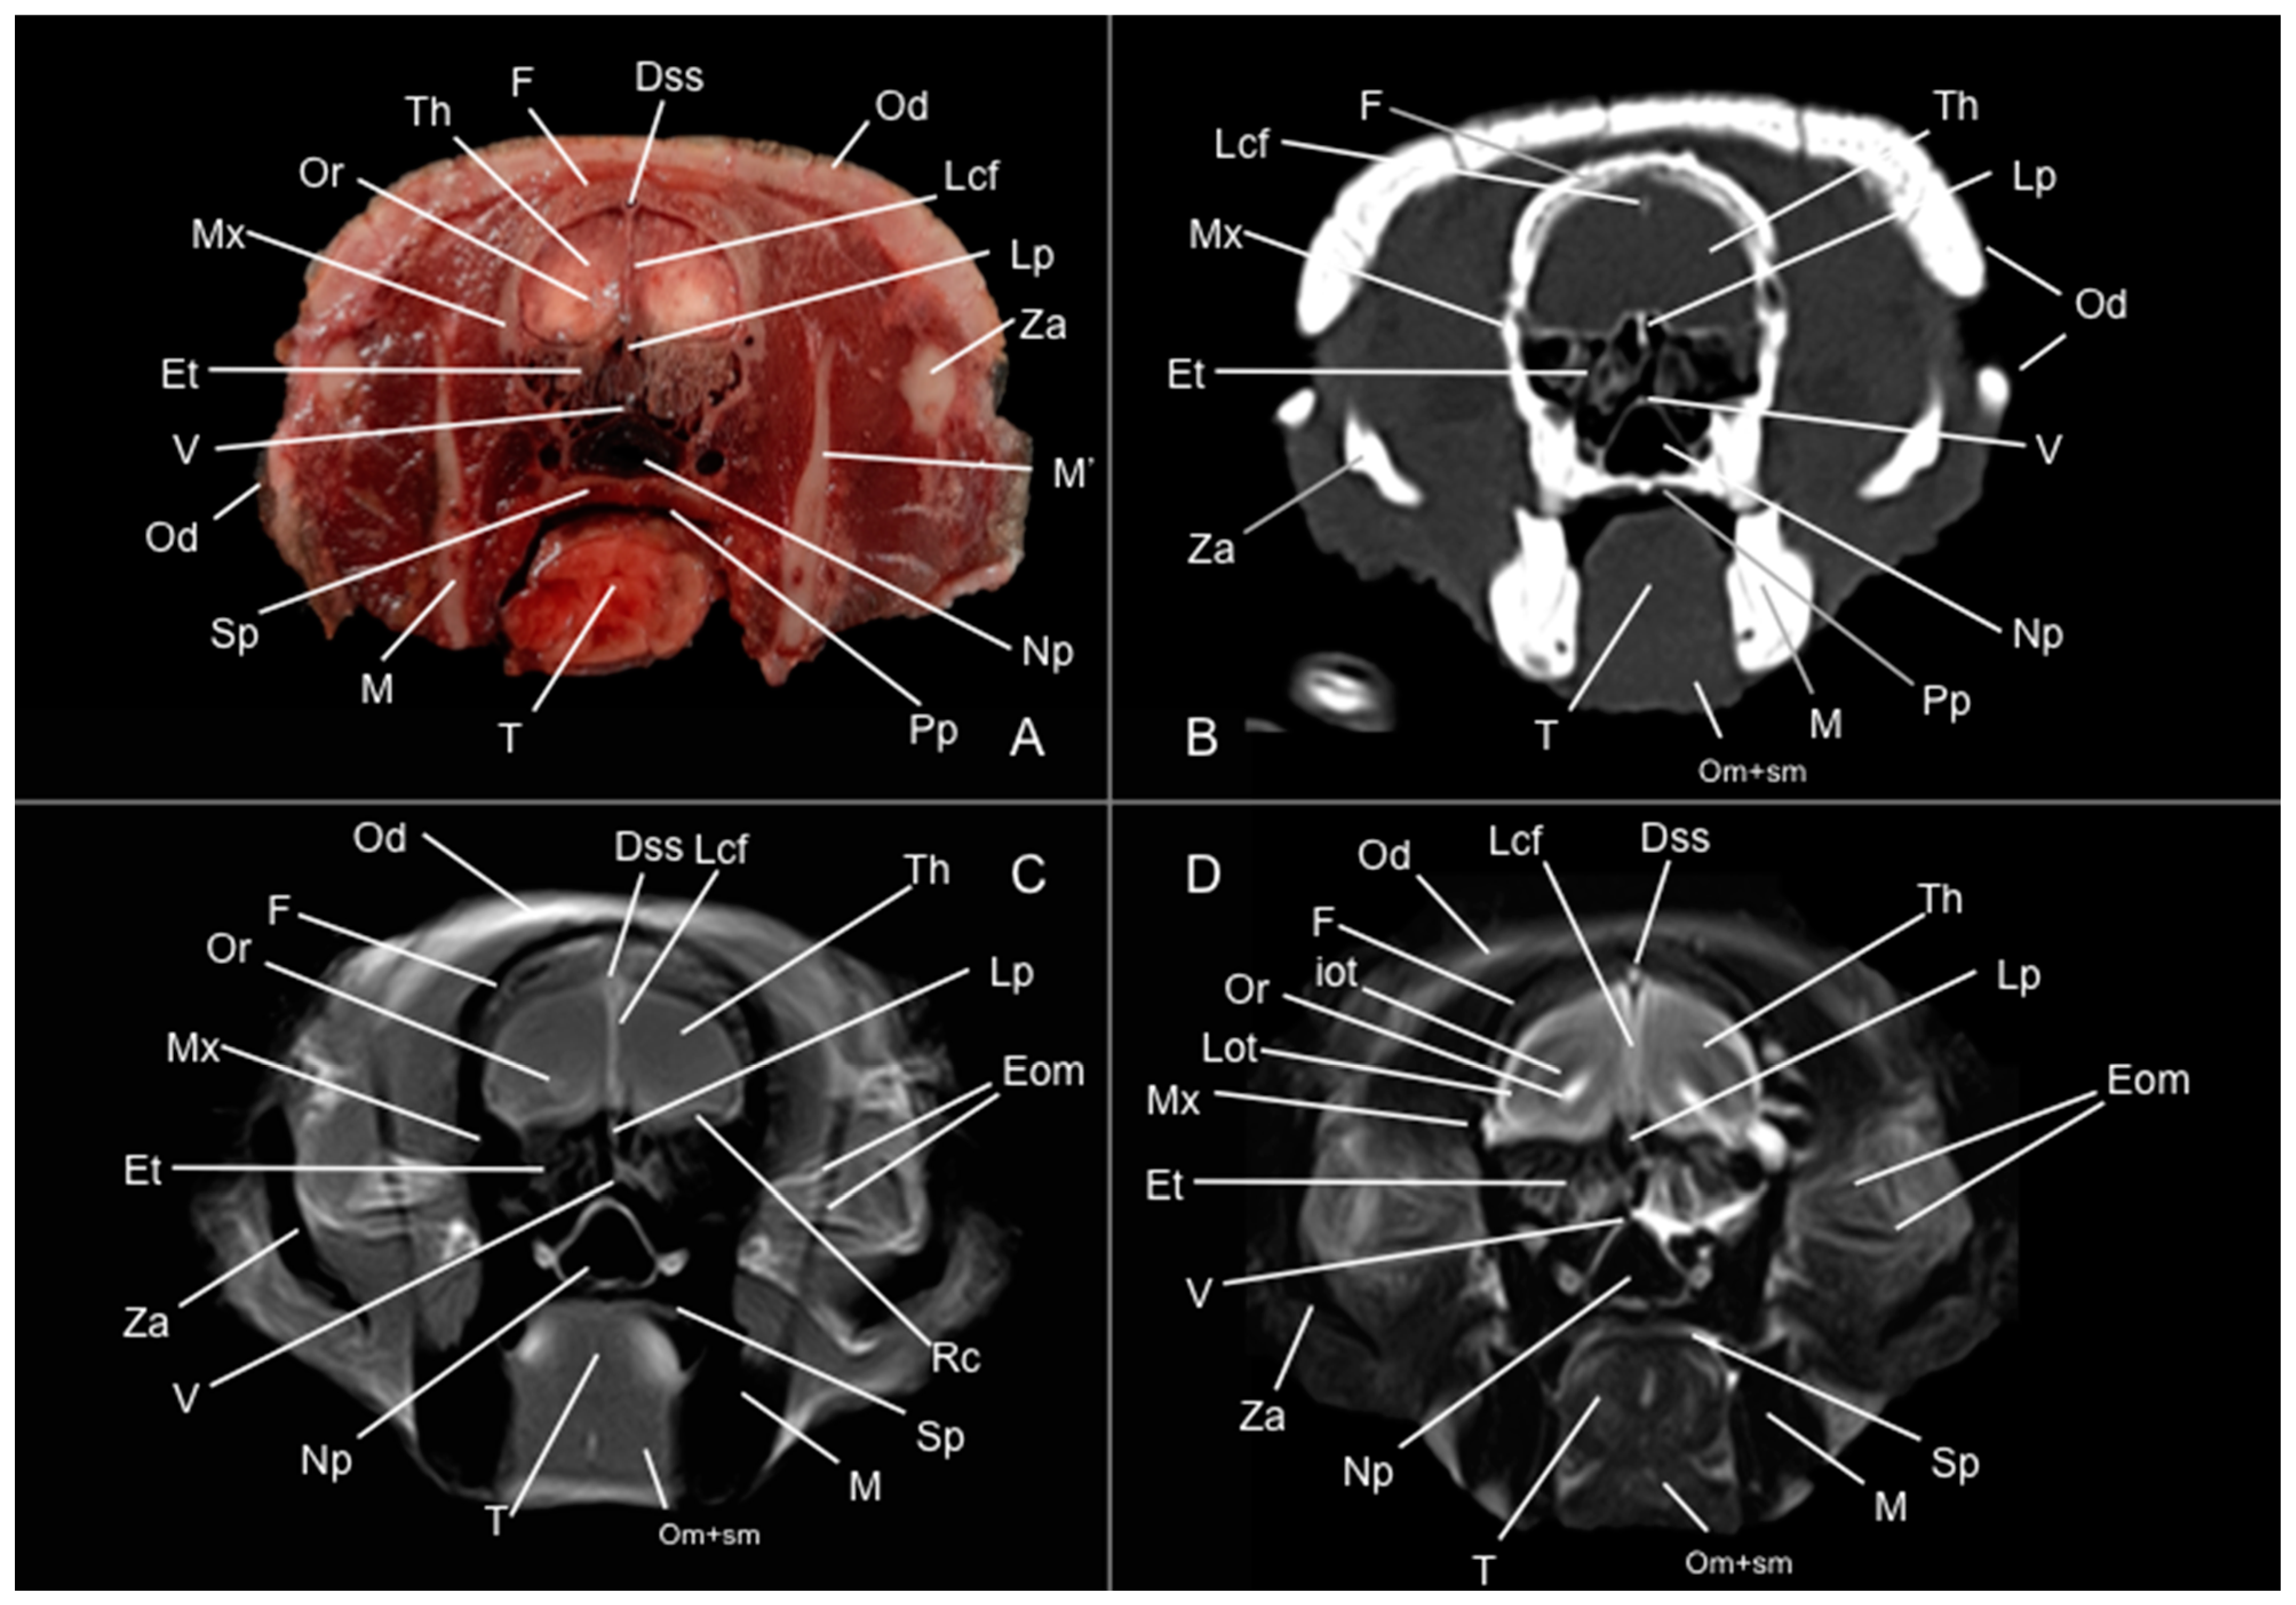

3.1. Anatomical Study

3.2. Computed Tomography Study

3.3. Magnetic Resonance Imaging (MRI)